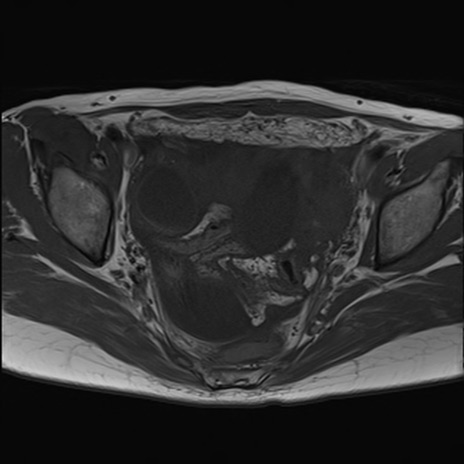

症例39 T1WI(横断像)

【症例】40歳代女性

【主訴】上下腹部痛

【現病歴】2日目から下腹部痛あり。夜間は痛みで眠れなかった。昨日より上腹部痛と下痢が出現。臥位で痛みは軽快したため、休んでいた。本日になって臥位でも立位でも痛みが強くなってきたため救急要請。

【既往歴】子宮内膜症

【身体所見】部:平坦・軟、左上下腹部に圧痛あり、反跳痛あり。

【データ】WBC 21800、CRP 26.78

MRI(4日後)